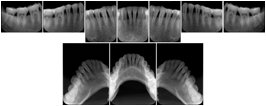

OO.1.2 Ophthalmology

1. A patient in rural Canada visits a general ophthalmologist and is found to have diabetic macular edema. The general ophthalmologist would like to discuss the case with a retina specialist before performing laser surgery. A fluorescein angiogram is done with multiple retinal images taken in a timed series after an intravenous injection. The images along with a Structured Display are shared via a Health Information Exchange with a retina specialist in Calgary, who opens them using his Ophthalmology EMR software and consults via phone with the general ophthalmologist. Both physicians view the images in the same layout so the retina specialist can provide accurate guidance for treating the patient.

2. A patient in rural Iowa visits his primary care physician for management of diabetes. Three non-mydriatic (patient's eyes are not dilated) photographs are taken of the back of each eye, and forwarded electronically along with a Structured Display to an ophthalmologist in Iowa City. The ophthalmologist reads the photos in an agreed upon layout so there is no mistake about what portion of which eye is being viewed. The ophthalmologist is able to tell the primary care physician that his patient does not need to come to Iowa City for face to face ophthalmologic care, but that there is a particular view of the left eye that should be photographed again in 6 months.

Ophthalmic Retinal Study Structured Display

Figure OO-3. Ophthalmic Retinal Study Structured Display